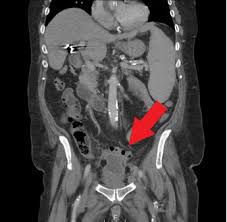

A pelvic abscess is a life-threatening collection of infected fluid in the pouch of Douglas, fallopian tube, ovary, or parametric tissue. Usually, a pelvic abscess occurs as a complication after operative procedures. It starts as pelvic cellulitis or hematoma spreads to parametrial tissue.